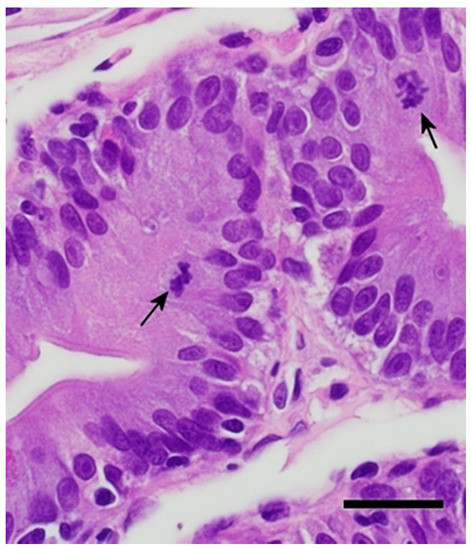

3.2. Pathogenesis of Isospora Amphiboluri